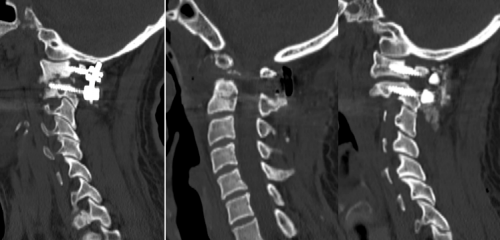

术后,在医护团队的悉心照顾下,患者康复顺利;复查CT、磁共振提示寰枢椎脱位完全复位,脊髓压迫得以充分解除。

图片

医生术后部分影像